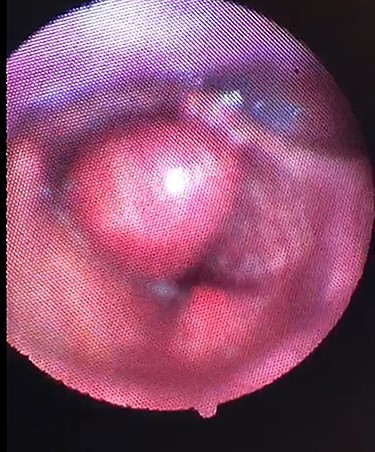

Clinical photograph showing the large cystic swelling arising from the right ventricle.

On examination, he was tachypnoeic, with a respiratory rate of 32 and oxygen saturations of 92% on room air. Although he was afebrile and haemodynamically stable, he was visibly exhausted, with accessory muscle use and stridulous breathing. There were no palpable swellings in the patient’s neck. Flexible nasoendoscopy showed a large submucosal swelling arising from the right vestibular fold, causing intermittent airway obstruction (Video) (Fig. 2). Laboratory markers were within normal range. Computed tomography of neck showed a well-defined, peripherally enhancing collection in right paraglottic space, extending from level of hyoid bone into the right laryngeal ventricle, with significant airway compromise at the level of the vocal cords (Figs 3 and 4).